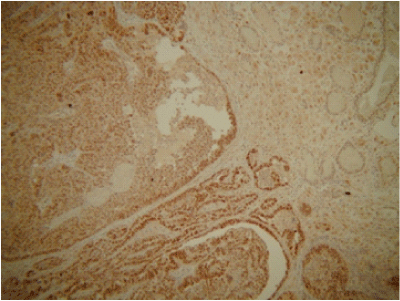

Histology analysis of the specimen showed poorly differentiated adenocarcinoma of endometrioid type, arising from the left fallopian tube with metastatic spread to ovaries, peritoneum and the appendix epiploicae as shown in the Figures 1–3. No metastatic spreads were found in the omentum. The cytology of the ascites was positive for adenocarcinoma cells. FIGO staging was of fallopian tube tumour stage IIB.

Figure 3 ER expression of the tumour. The tumour cells show strong positivity for ER receptors.